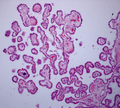

Choroid Plexus Histology 40x